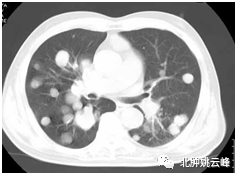

科普:什么是结直肠癌肺转移,结直肠癌肺转移还能活多久?...

肝转移?腹膜转移?晚期大肠癌(结直肠癌)就“无可救药” 了吗?...